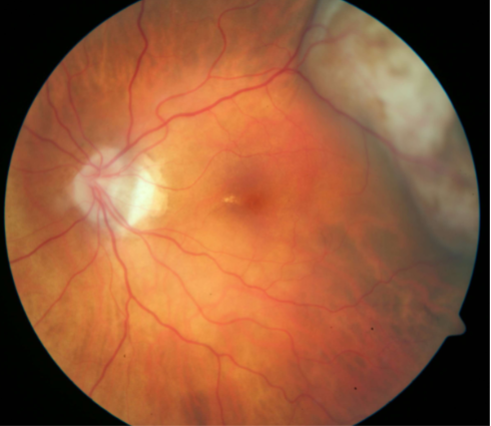

solitary choroidal hemangioma

choroidal hemangioma

choroidal hemangioma

choroidal hemangioma

choroidal hemangioma

choroidal hemangioma